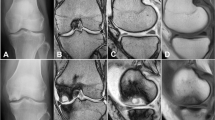

The extent of degeneration of the external meniscus and its possible progression were investigated with the classification system described and established by Stoller et al. [27]. According to Stoller, grade 0 indicates a normal finding, grade 1 corresponds to punctate elevated signals with no connection to the meniscal surface, grade 2 indicates a linear signal elevation with no contact with the articular meniscal surface, and grade 3 indicates a linear signal elevation with at least one point of contact with the meniscal surface.

Degeneration of the lateral meniscus

23 patients were included in the evaluation of degeneration according to the Stoller classification. One follow-up MRI could not be accurately assessed because the image quality was poor.

According to the Stoller classification, we also found significant degeneration in the region of the anterior horn (p < 0.01) as in the pars intermedia (p = 0.021) and the posterior horn (p < 0.01). For details, see Tables 2, 3 and 4.

In a large number of subjects, progression in the sense of the Stoller classification, up to manifest tears, was observed according to the imaging data. On the cellular level, Madry et al. [17] also detected a reduction in the number of cells in the region of the external meniscus in the group of patients treated with overcorrection, whereas the group with a neutral axis showed no such change. MR-tomography-detected degeneration may be the long-term result of this loss of cells because the follow-up period was longer in this study. This is particularly important in view of the high correlation between meniscal damage and cartilage damage [15]. The meniscus protects the underlying articular cartilage, and if it is cracked, the incidence of cartilage damage increases significantly [10]. Spahn et al. [26] showed that degenerative meniscal damage is associated with degenerative cartilage damage and that cartilage damage is always associated with isolated degenerative meniscal damage. Furthermore, Englund et al. [8] showed that damage to the meniscal tissue has an systemic effect on the development of osteoarthritis.

It was possible to determine whether the degeneration observed in this study was truly caused by the after-effects of HTO or whether it was a normal sign of aging. Englund et al. [7] examined 991 random subjects, aged from 50 to 90 years, with meniscal damage. They defined ‘damage’ as an elevated signal intensity in meniscal tissue associated with any surface of the meniscus, as in Stoller grades 2 and 3. The prevalence of meniscal damage in the lateral meniscus ranged from 9% (men) to 11% (women). Compared with the findings of the present study, it seems plausible that the reported degeneration was not merely caused by aging because the rate of damage classified Stoller grade 2 or 3 in a younger population was 34.8% when averaged over all parts of the meniscus.